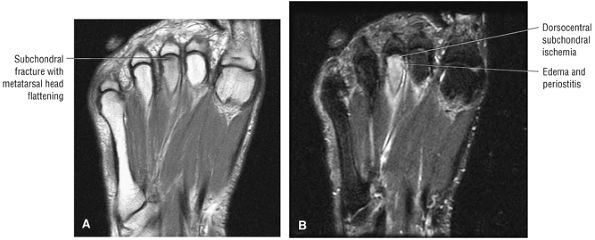

Stage I: Subchondral trabecular compression. Radiograph results are negative, bone scans are posi-tive, and marrow edema is seen on MR imaging (Fig. 5.95).

Stage IIA: A subchondral cyst (Fig. 5.96)

Stage IIB: Incomplete separation of the fragment (Fig. 5.97)

Stage III: Fluid around a nondetached, nondisplaced fragment (Figs. 5.98 and 5.99)

Stage IV: A displaced fragment (Fig. 5.100)